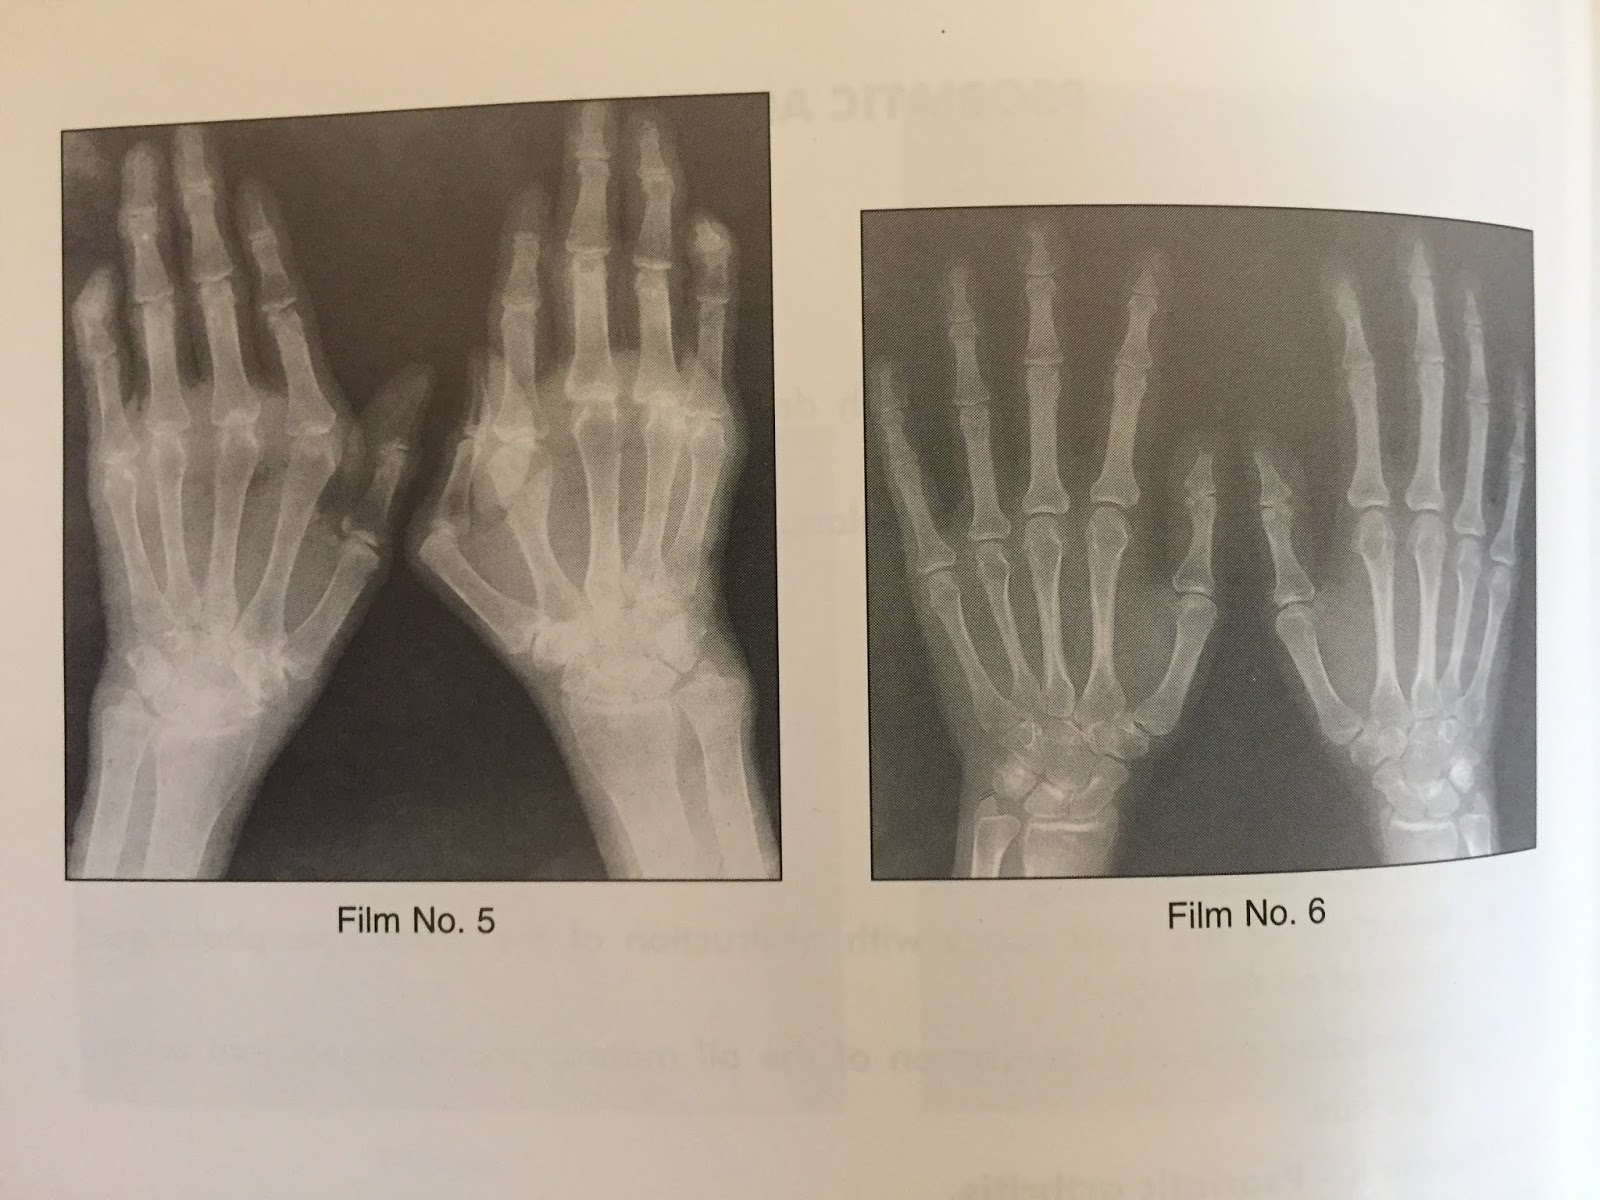

Psoriatic Arthritis Finger X Ray . Up to 30% of patients with psoriasis develop psoriatic. Although radiography is the most frequently performed imaging examination for ra and psa,. Psoriasis is a common skin disease. Psoriatic arthritis is diagnosed using radiological imaging. A person with psa may also have skin changes. Psoriatic arthritis (psa) is a type of inflammatory arthritis that causes swelling, stiffness, redness, pain, and damage to the skin, nails, joints, and more.

Diagnostics Free FullText Radiographic Findings of Inflammatory Psoriatic Arthritis Finger X Ray Psoriasis is a common skin disease. A person with psa may also have skin changes. Up to 30% of patients with psoriasis develop psoriatic. Although radiography is the most frequently performed imaging examination for ra and psa,. Psoriatic arthritis is diagnosed using radiological imaging. Psoriatic arthritis (psa) is a type of inflammatory arthritis that causes swelling, stiffness, redness, pain, and. Psoriatic Arthritis Finger X Ray.

Plain Film, Radiography, Of Both Hands, Arthritis Stock Photo Image Psoriatic Arthritis Finger X Ray Although radiography is the most frequently performed imaging examination for ra and psa,. Psoriasis is a common skin disease. Psoriatic arthritis (psa) is a type of inflammatory arthritis that causes swelling, stiffness, redness, pain, and damage to the skin, nails, joints, and more. A person with psa may also have skin changes. Psoriatic arthritis is diagnosed using radiological imaging. Up. Psoriatic Arthritis Finger X Ray.